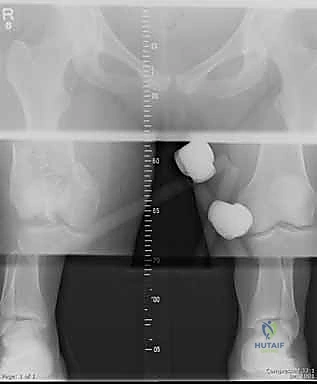

يمر المحور الميكانيكي لعظم الفخذ من مركز رأس عظم الفخذ إلى مركز الركبة، وعادة ما ينحرف بمقدار 3 درجات عن الخط العمودي. يستمر هذا المحور بعد ذلك إلى مركز الكاحل، ليحدد المحور الميكانيكي للطرف بأكمله. في المقابل، يظهر المحور التشريحي لعظم الفخذ مع حوالي 9 درجات من الانحراف الخارجي (Valgus) بالنسبة لمحور مفصل الركبة.

عند حدوث كسر في هذه المنطقة، تختل هذه المحاور الدقيقة، مما يؤدي إلى توزيع غير متساوٍ للضغط على غضاريف الركبة. إذا لم يتم إصلاح هذا الخلل جراحياً بدقة متناهية، فإن المريض سيكون عرضة للإصابة بخشونة الركبة المبكرة (Post-traumatic Osteoarthritis).

- الأشعة السينية (X-Rays): أخذ صور من زوايا متعددة (أمامي خلفي، وجانبي) لتحديد موقع الكسر ونوعه.

- الأشعة المقطعية (CT Scan): وهي ضرورية جداً في كسور عظم الفخذ البعيدة، خاصة إذا كان الكسر يمتد إلى داخل مفصل الركبة (Intra-articular fractures). تساعد الأشعة المقطعية الدكتور هطيف على بناء نموذج ثلاثي الأبعاد للكسر، مما يسهل التخطيط الجراحي وتحديد أماكن وضع المسامير بدقة.